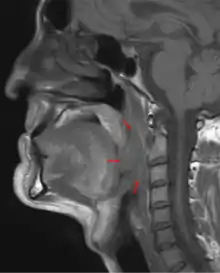

| 3D medical illustration showing the cancer formation in the tissues of the oropharynx | |